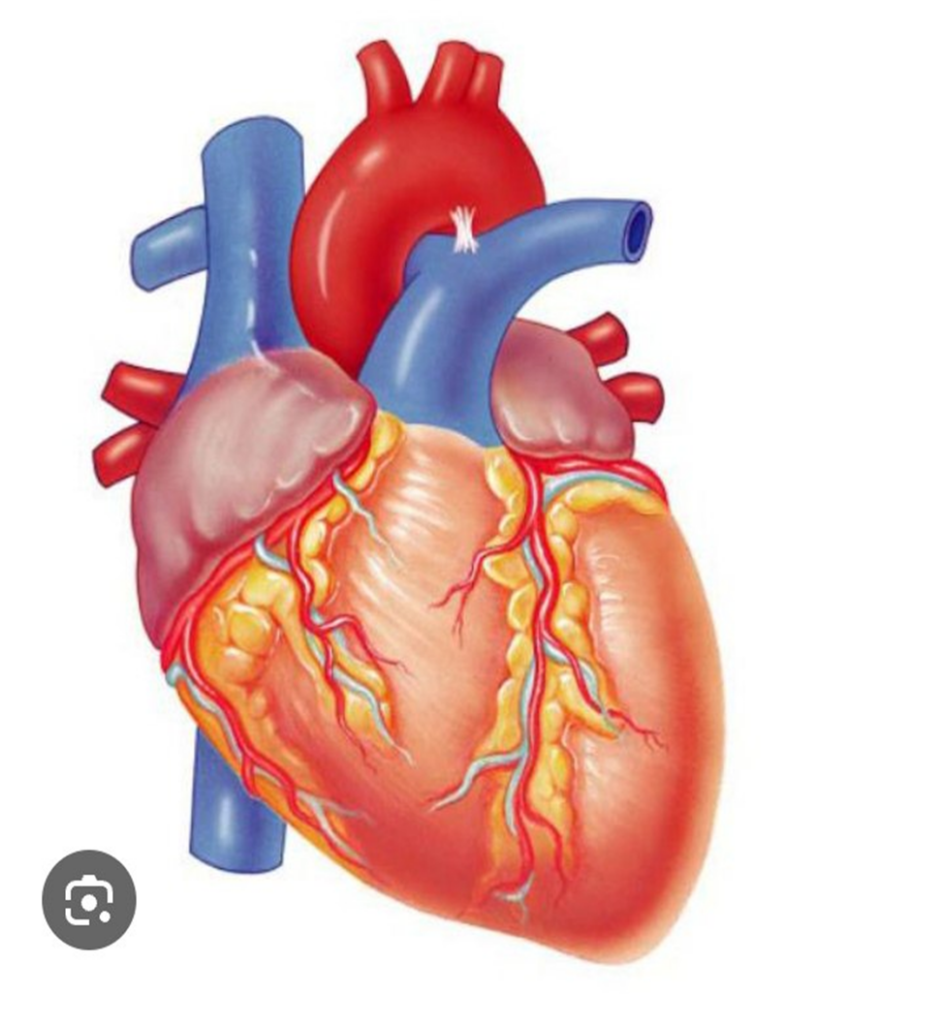

O’quvchilarga yurak rasmi chizilgan plakat, ingichka shlanglar, shprist, rangli suv beriladi ular shu videoda: https://youtube.com/watch?v=b20Jgm6u6-U&si=rVnDkfZHUIJz4SVA ko’rsatilgandek ushbu materiallardan foydalanib qon aylanish jarayonini aks ettiruvchi maket tayyorlaydilar.

“O‘rnini top” didaktik o‘yini tashkil etiladi: doskaga yurakning yirik sxematik tasviri tushirilgan plakat ilib qo‘yiladi. O‘quvchilarga yurakning quyidagi anatomik tuzilmalari nomlari yozilgan yopishqoq kartochkalar tarqatiladi: o‘ng va chap bo‘lmachalar, o‘ng va chap qorinchalar, yuqori va pastki kovak venalar, aorta, chap o‘pka arteriyasi, o‘ng o‘pka venalari, ikki tavaqali (mitral) klapan, uch tavaqali (trikuspid) klapan hamda yarim oysimon klapanlar. O‘quvchilar navbat bilan doskaga chiqib, kartochkada ko‘rsatilgan yurak tuzilmasining anatomik jihatdan to‘g‘ri joylashuvini aniqlab, plakatga joylashtiradilar.